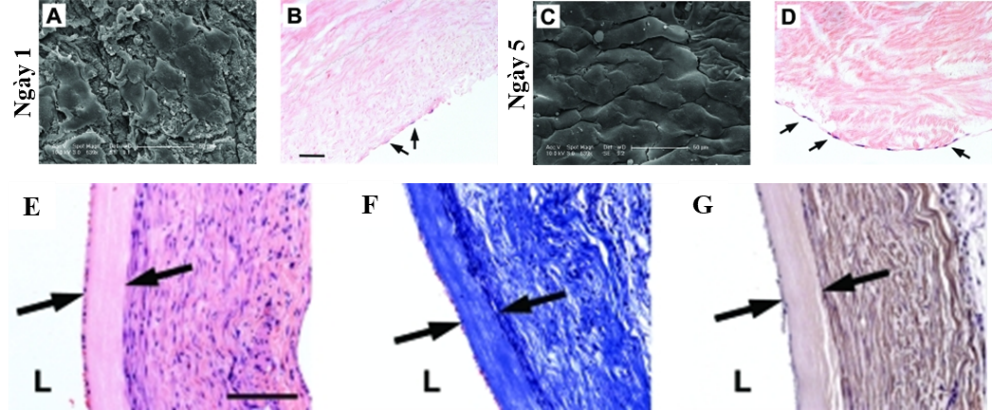

Một số nghiên cứu gần đây đã phát triển việc sử dụng các động mạch dây rốn (UCA) được khử tế bào để tạo nguồn cung cấp các SDVG. Các mạch khử tế bào này vẫn chứa thành phần chất nền ngoại bào tự nhiên giúp duy trì cấu trúc và tính chất cơ học của mô mạch. Các mạch máu này có thể được tái bổ sung bằng nhiều loại tế bào tim mạch khác nhau, bao gồm tế bào nội mô, tế bào tiền thân và tế bào cơ tim để tạo ra các mô chức năng (Hình 4).

Quá trình khử tế bào của các mạch máu có nguồn gốc tự nhiên cũng làm giảm tính sinh miễn dịch của chúng, giúp thuận lợi hơn cho việc ghép mạch đồng loài. Ngoài ra, các mô bị khử tế bào vẫn có khả năng sửa chữa, tăng trưởng và tái cấu trúc trong cơ thể. Những phát hiện này cho thấy rằng quá trình khử tế bào của các vật liệu sinh học sẵn có trong tự nhiên là một phương pháp đầy hứa hẹn để chuẩn bị các SDVG.

Tuy nhiên, việc sử dụng trực tiếp các mạch khử tế bào để ghép vẫn còn nhiều thách thức liên quan đến hiện tượng phình động mạch, rối loạn huyết động và tắc nghẽn mạch máu, dẫn đến tỷ lệ sống sót của vật chủ thấp. Trong nghiên cứu của Gui và các cộng sự, các mạch dây rốn khử tế bào trước ghép có đường kính trong là 1,5 mm (tại áp lực zero), khá tương đồng với kích thước động mạch chuột cống (khoảng 1 mm). Tuy nhiên, đường kính mạch tăng lên nhanh chóng và đạt xấp xỉ 4,5 mm sau khi ghép (Hình 5).

Do đường kính không khớp, kiểm tra siêu âm động mạch chủ cho thấy dòng chảy bị rối loạn gần vùng nối và lưu lượng dòng chảy trong mạch ghép thấp hơn đáng kể so với động mạch của vật chủ. Tỷ lệ huyết khối cấp tính ở những mạch ghép khử tế bào có lẽ là do thiếu lớp nội mạc và sự tiếp xúc của collagen trên bề mặt mạch với dòng máu chảy không được chống đông. Sự giãn thành mạch cũng có thể xảy ra bởi sự suy yếu trong cấu trúc thành mạch do thiếu sự hiện diện của tế bào. Những vấn đề trên cho thấy, để mạch máu dây rốn có thể được sử dụng như nguồn ghép các mạch máu nhỏ, vẫn cần phải có những nghiên cứu để giải quyết được những nhược điểm của động mạch khử tế bào.

Sau một quá trình nghiên cứu và thử nghiệm, chúng tôi đã xây dựng được một quy trình xử lý mạch tiền ghép và quy trình ghép mạch dị loài từ động mạch dây rốn vào động mạch chủ bụng dưới thận chuột cống trắng thành công. Các động mạch dây rốn sau khi thu nhận và xử lý tiền ghép không gây kích thích tăng sinh tế bào T khi tiếp xúc với các tế bào bạch cầu đơn nhân của máu chuột cống, không kích thích biểu hiện các yếu tố chỉ thị trạng thái hoạt hóa của tế bào T (còn gọi là tế bào lympho T – là một loại bạch cầu thuộc dòng tế bào lympho, đóng vai trò quan trọng trong hệ thống miễn dịch đáp ứng của cơ thể) như IL1-β, IFN-α, và TNFα. Hơn nữa, phân tích giải phẫu bệnh cho thấy chỉ có sự đáp ứng viêm nhẹ khi mạch dây rốn được cấy vào lớp mỡ dưới da chuột cống sau 30 ngày. Những kết quả này cho thấy, động mạch dây rốn tươi có tính sinh miễn dịch thấp, phù hợp cho việc ghép trên chuột cống.

Kết quả ghép dị loài cho thấy, 100% chuột ghép mạch dây rốn người (10/10) đều có khả năng sống trên 4 tuần sau ghép. Đáng chú ý, không nhận thấy hiện tượng tắc mạch hay huyết khối xảy ra trong mạch ghép dựa trên các kết quả siêu âm định kỳ sau 3, 7, 21, và 30 ngày sau ghép. Thêm vào đó, mặc dù có sự không hoàn toàn phù hợp về kích thước, do đường kính mạch dây rốn lớn hơn động mạch chủ của chuột cống, tương tự như các báo cáo đã công bố, nhưng trong nghiên cứu này, kết quả siêu âm cho thấy đường kính trong lòng mạch khá ổn định theo thời gian, không thấy sự tăng rõ rệt về kích thước như trong nghiên cứu của Gui và cộng sự. Đồng thời, lưu lượng máu lưu thông trong mạch ghép khá tương đồng với động mạch chủ chuột tại hai đầu nối mạch. Đánh giá vi thể, các chỉ số sinh lý, hóa sinh, và phản ứng miễn dịch cho thấy mảnh ghép hòa hợp với cơ thể nhận và thực hiện chức năng như các mạch máu bình thường của cơ thể. Các kết quả đánh giá hoạt động chức năng vận động của chuột ghép cho thấy sự tương đồng với đối chứng trong suốt quá trình thí nghiệm. Quy trình ghép và chuột ghép dị loài đã được nhóm nghiên cứu đăng ký sáng chế với Cục Sở hữu trí tuệ (đã được chấp nhận đơn và đang trong quá trình xem xét cấp bằng).